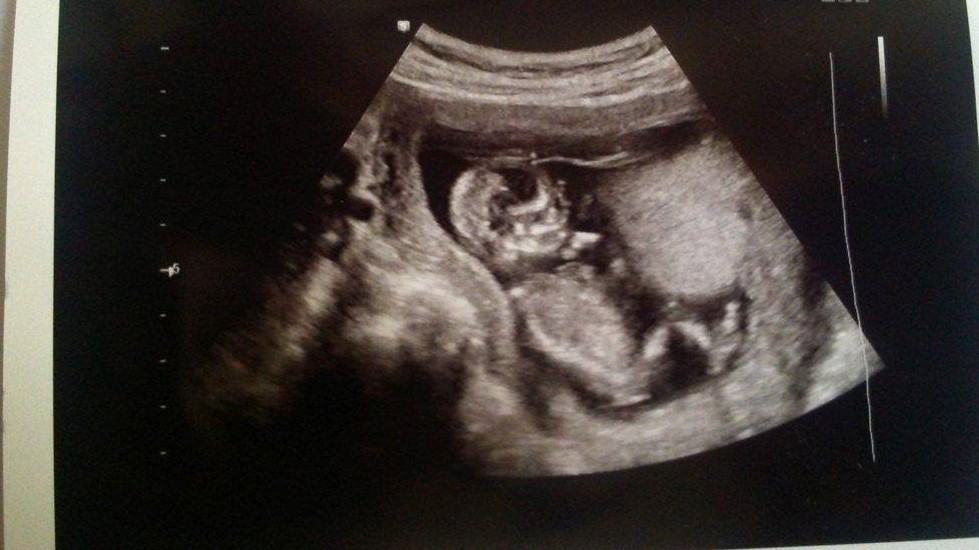

Please. Any guesses on a boy or girl please? Skull/Nub Theory?

Are there any signs at all in my scan photos about whether I'm carrying a boy or a girl?

I know they aren't the clearest photos, but they're the only ones I have.

20 weeks

Attachment 36256